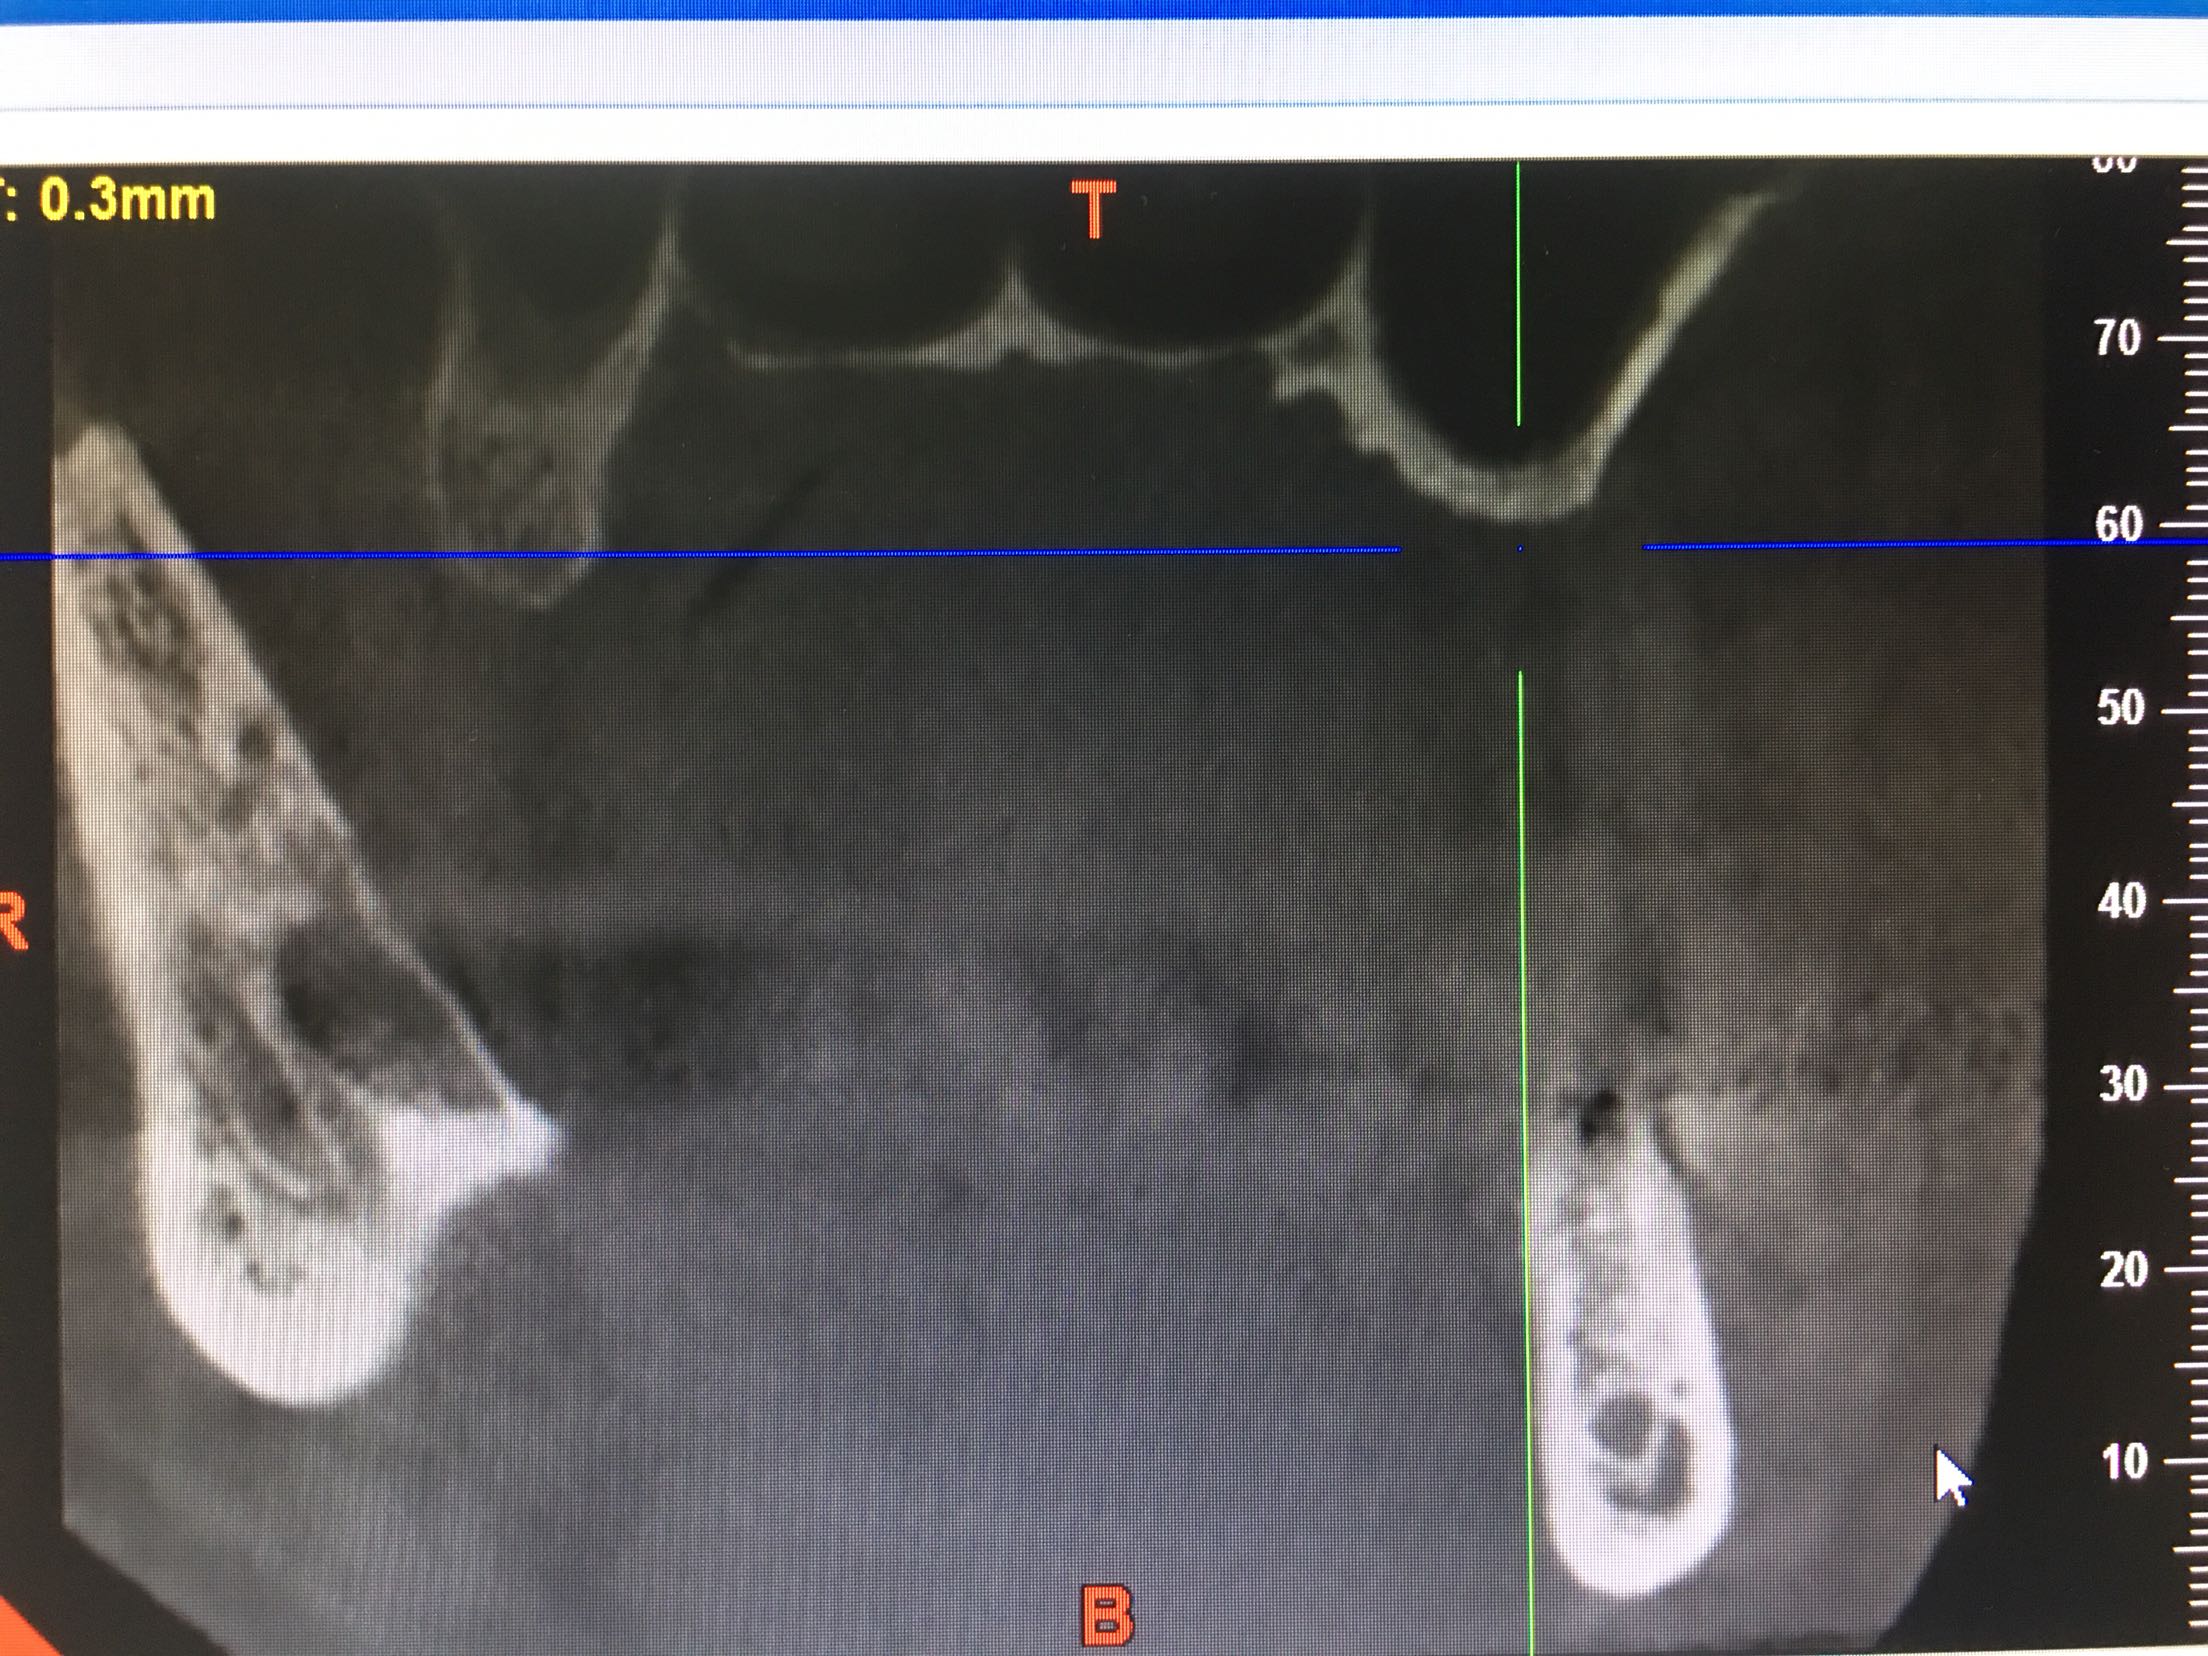

上颌窦底27只有2.4mm,26有4mm

期待半年后的效果,最主要的挑战:每天15支吸烟史,上颌窦黏膜菲薄,27牙上颌窦底只有2.4mm,超出即刻种植5mm的界限!